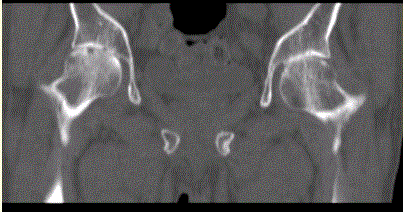

问题 患者女,53岁,双髋关节痛。双髋关节CT平扫冠状重组影像如下图。 髋关节类风湿性关节炎的表现包括

选项 A.关节间隙均匀性狭窄 B.关节边缘骨赘形成 C.关节周围骨质疏松 D.股骨头轴向移位 E.关节表面骨侵蚀 F.关节腔滑膜增生 G.MRI动态增强检查可以判断病变的活动性 H.关节面下增生、硬化

答案 ACDEFG

解析 ACDEFG